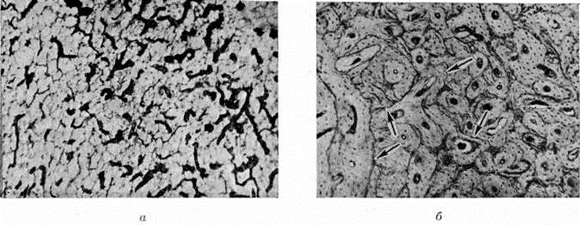

В результате костное вещество убывает, что выражается в остеопорозе (смотри полный свод знаний). В других — зрелая костная ткань в значительной мере замещается незрелым патологический костным веществом — остеоидом, например, при рахите, или в связи с ускорением темпов перестройки новые костные структуры имеют примитивное строение (рисунок 1, а), что характерно для паратиреоидной Остеодистрофия Иногда вновь образованная костная ткань выглядит относительно зрелой, но в связи с ускорением темпов рассасывания и созидания в костном веществе появляется большое число линий резорбции, а также «обломочных» структур в виде островков старых костных пластин среди новообразованной костной ткани. Реже Остеодистрофия выражается в усилении костеобразовательных процессов, в результате чего развивается остеосклероз (смотри полный свод знаний), например, в некоторых случаях почечной Остеодистрофия Присутствующая в костях кроветворная ткань замещается волокнистой соединительной, нередко остеобластической, тканью (рисунок 1, б).

Рис. 1.

Микропрепараты костной ткани при паратиреоидной остеодистрофии: а — замещение зрелой пластинчатой костной ткани (I) незрелой, с новообразованными примитивными костными балками (2); окраска гематоксилин-эозином; ½ 75; б — частичное замещение кроветворного костного мозга (1) волокнистой соединительной тканью (2); окраска гематоксилин-эозином; ½ 75; в — многоядерные клетки типа остеокластов (указаны стрелками), содержащиеся в «бурой» опухоли; окраска гематоксилин-эозином; ½ 300.